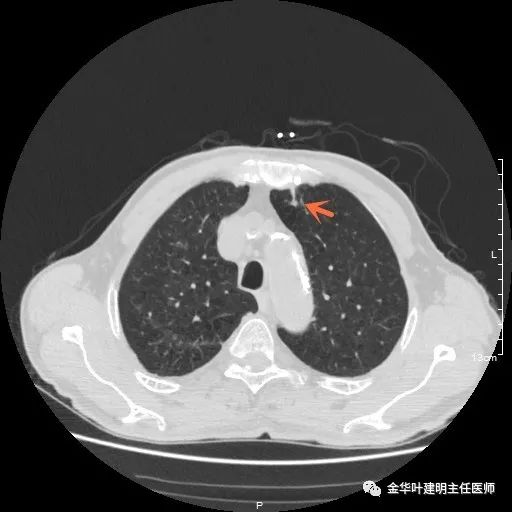

以上示右肺中叶病灶3。是混合磨玻璃结节,位置差,邻近肺门部,无法局部楔形切除,抗炎治疗后靶扫描显示了更清楚的细节,是典型的肺癌影像特征(此处未另提供)。从单病灶来看,需要行右肺中叶切除并清扫淋巴结才能得以治疗。